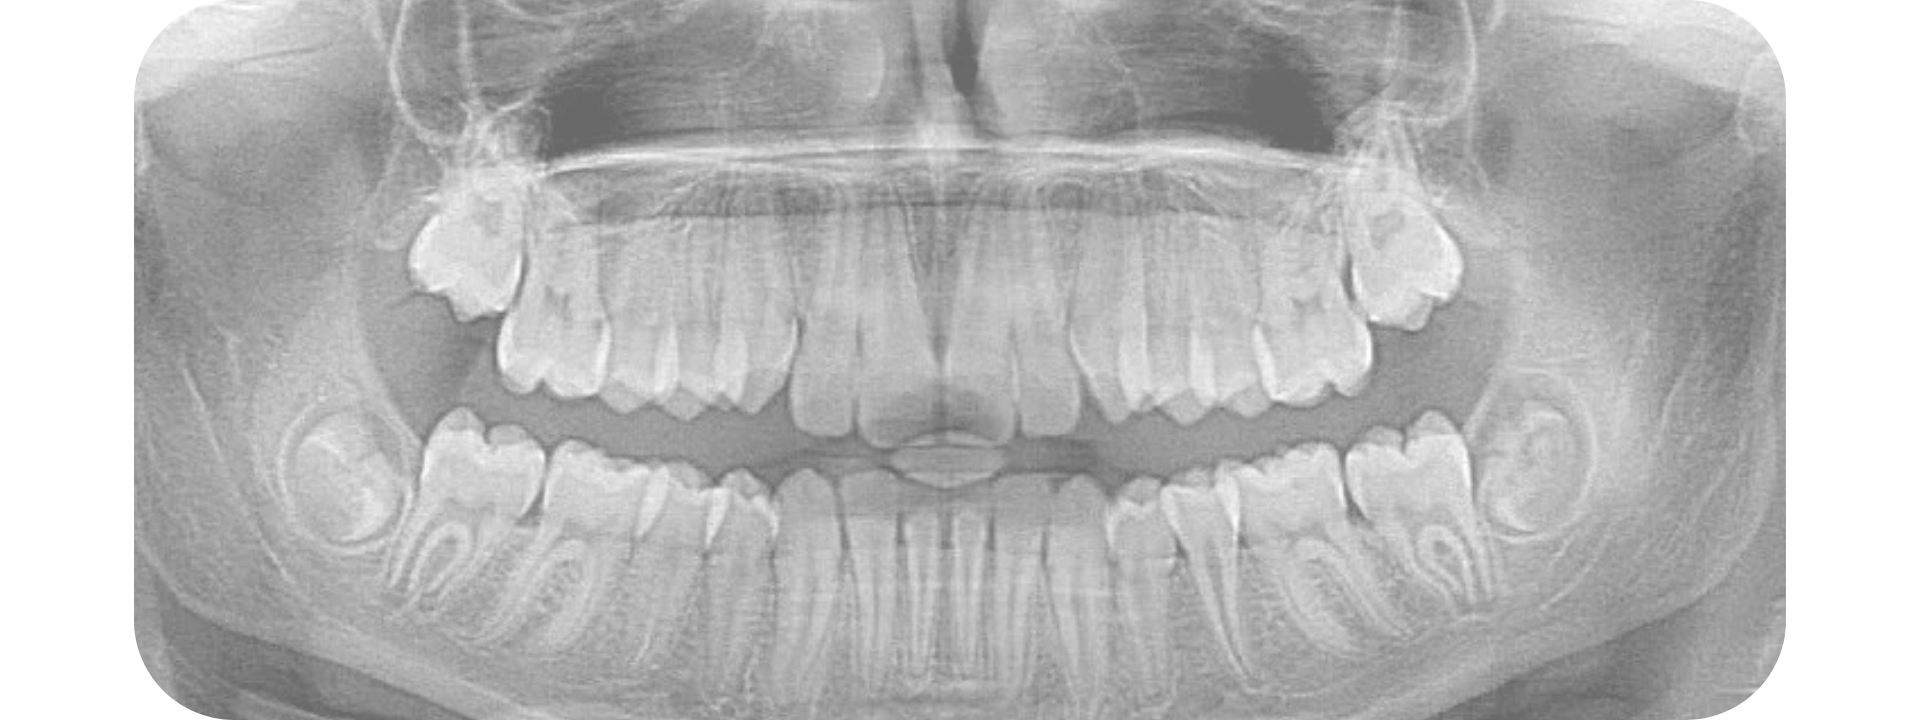

Radiografía lateral de cráneo, panorámica y carpal

Estudios iniciales para ortodoncia